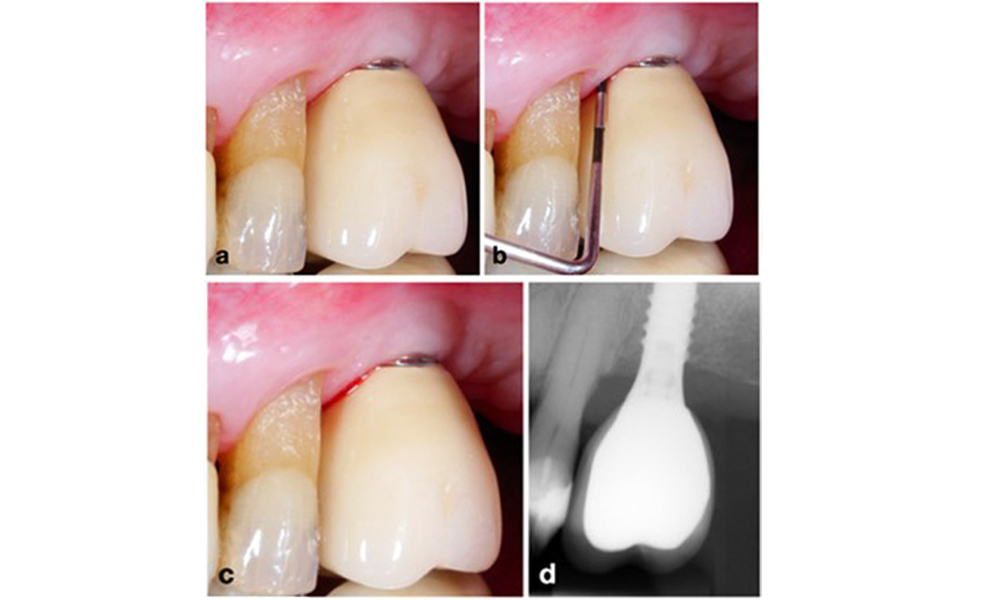

Периимплантитът се идентифицира чрез (1) признаци на възпаление, подобни на мукозит, (2) рентгенографски данни за загуба на кост след първоначалното заздравяване и (3) увеличаване на дълбочината на сондиране в сравнение с измерванията, направени малко след поставянето на протезната реконструкция (фигура 2) . При липса на предишни рентгенографии, рентгенографско костно ниво ≥ 3 mm и кървене при сондиране и дълбочина на сондиране ≥ 6 mm показват периимплантит.

Възстановяване на цяла зъбна дъга с различна степен на периимплантит при някои от имплантите. Имплантът в позиция 21 е силно засегнат с дълбочина на сондиране до 9 mm (a), кървене при сондиране и образуване на гной в периимплантния сулкус и вестибуларна фистула (b–c); рентгеновата снимка показва приблизително 50% костна загуба за импланта с периимплантит в позиция 21, докато имплантът в позиция 23 показва само ограничена костна загуба, съответстваща приблизително на това, което може да се очаква след първоначалното заздравяване за този тип импланти (d).

Фигура 2. Възстановяване на цяла зъбна дъга с различна степен на периимплантит при някои от имплантите. Имплантът в позиция 21 е силно засегнат с дълбочина на сондиране до 9 mm (a), кървене при сондиране и образуване на гной в периимплантния сулкус и вестибуларна фистула (b–c); рентгеновата снимка показва приблизително 50% костна загуба за импланта с периимплантит в позиция 21, докато имплантът в позиция 23 показва само ограничена костна загуба, съответстваща приблизително на това, което може да се очаква след първоначалното заздравяване за този тип импланти (d).

Очакваната костна загуба след първоначалното заздравяване се дължи на маргиналното костно ремоделиране и варира в зависимост от фактори като имплантна система или типа имплант. Например загуба на 1–2 mm кост обикновено се счита за „нормална“ за импланти на нивото на костта с външна връзка (фигура 2d, имплант в позиция 23).